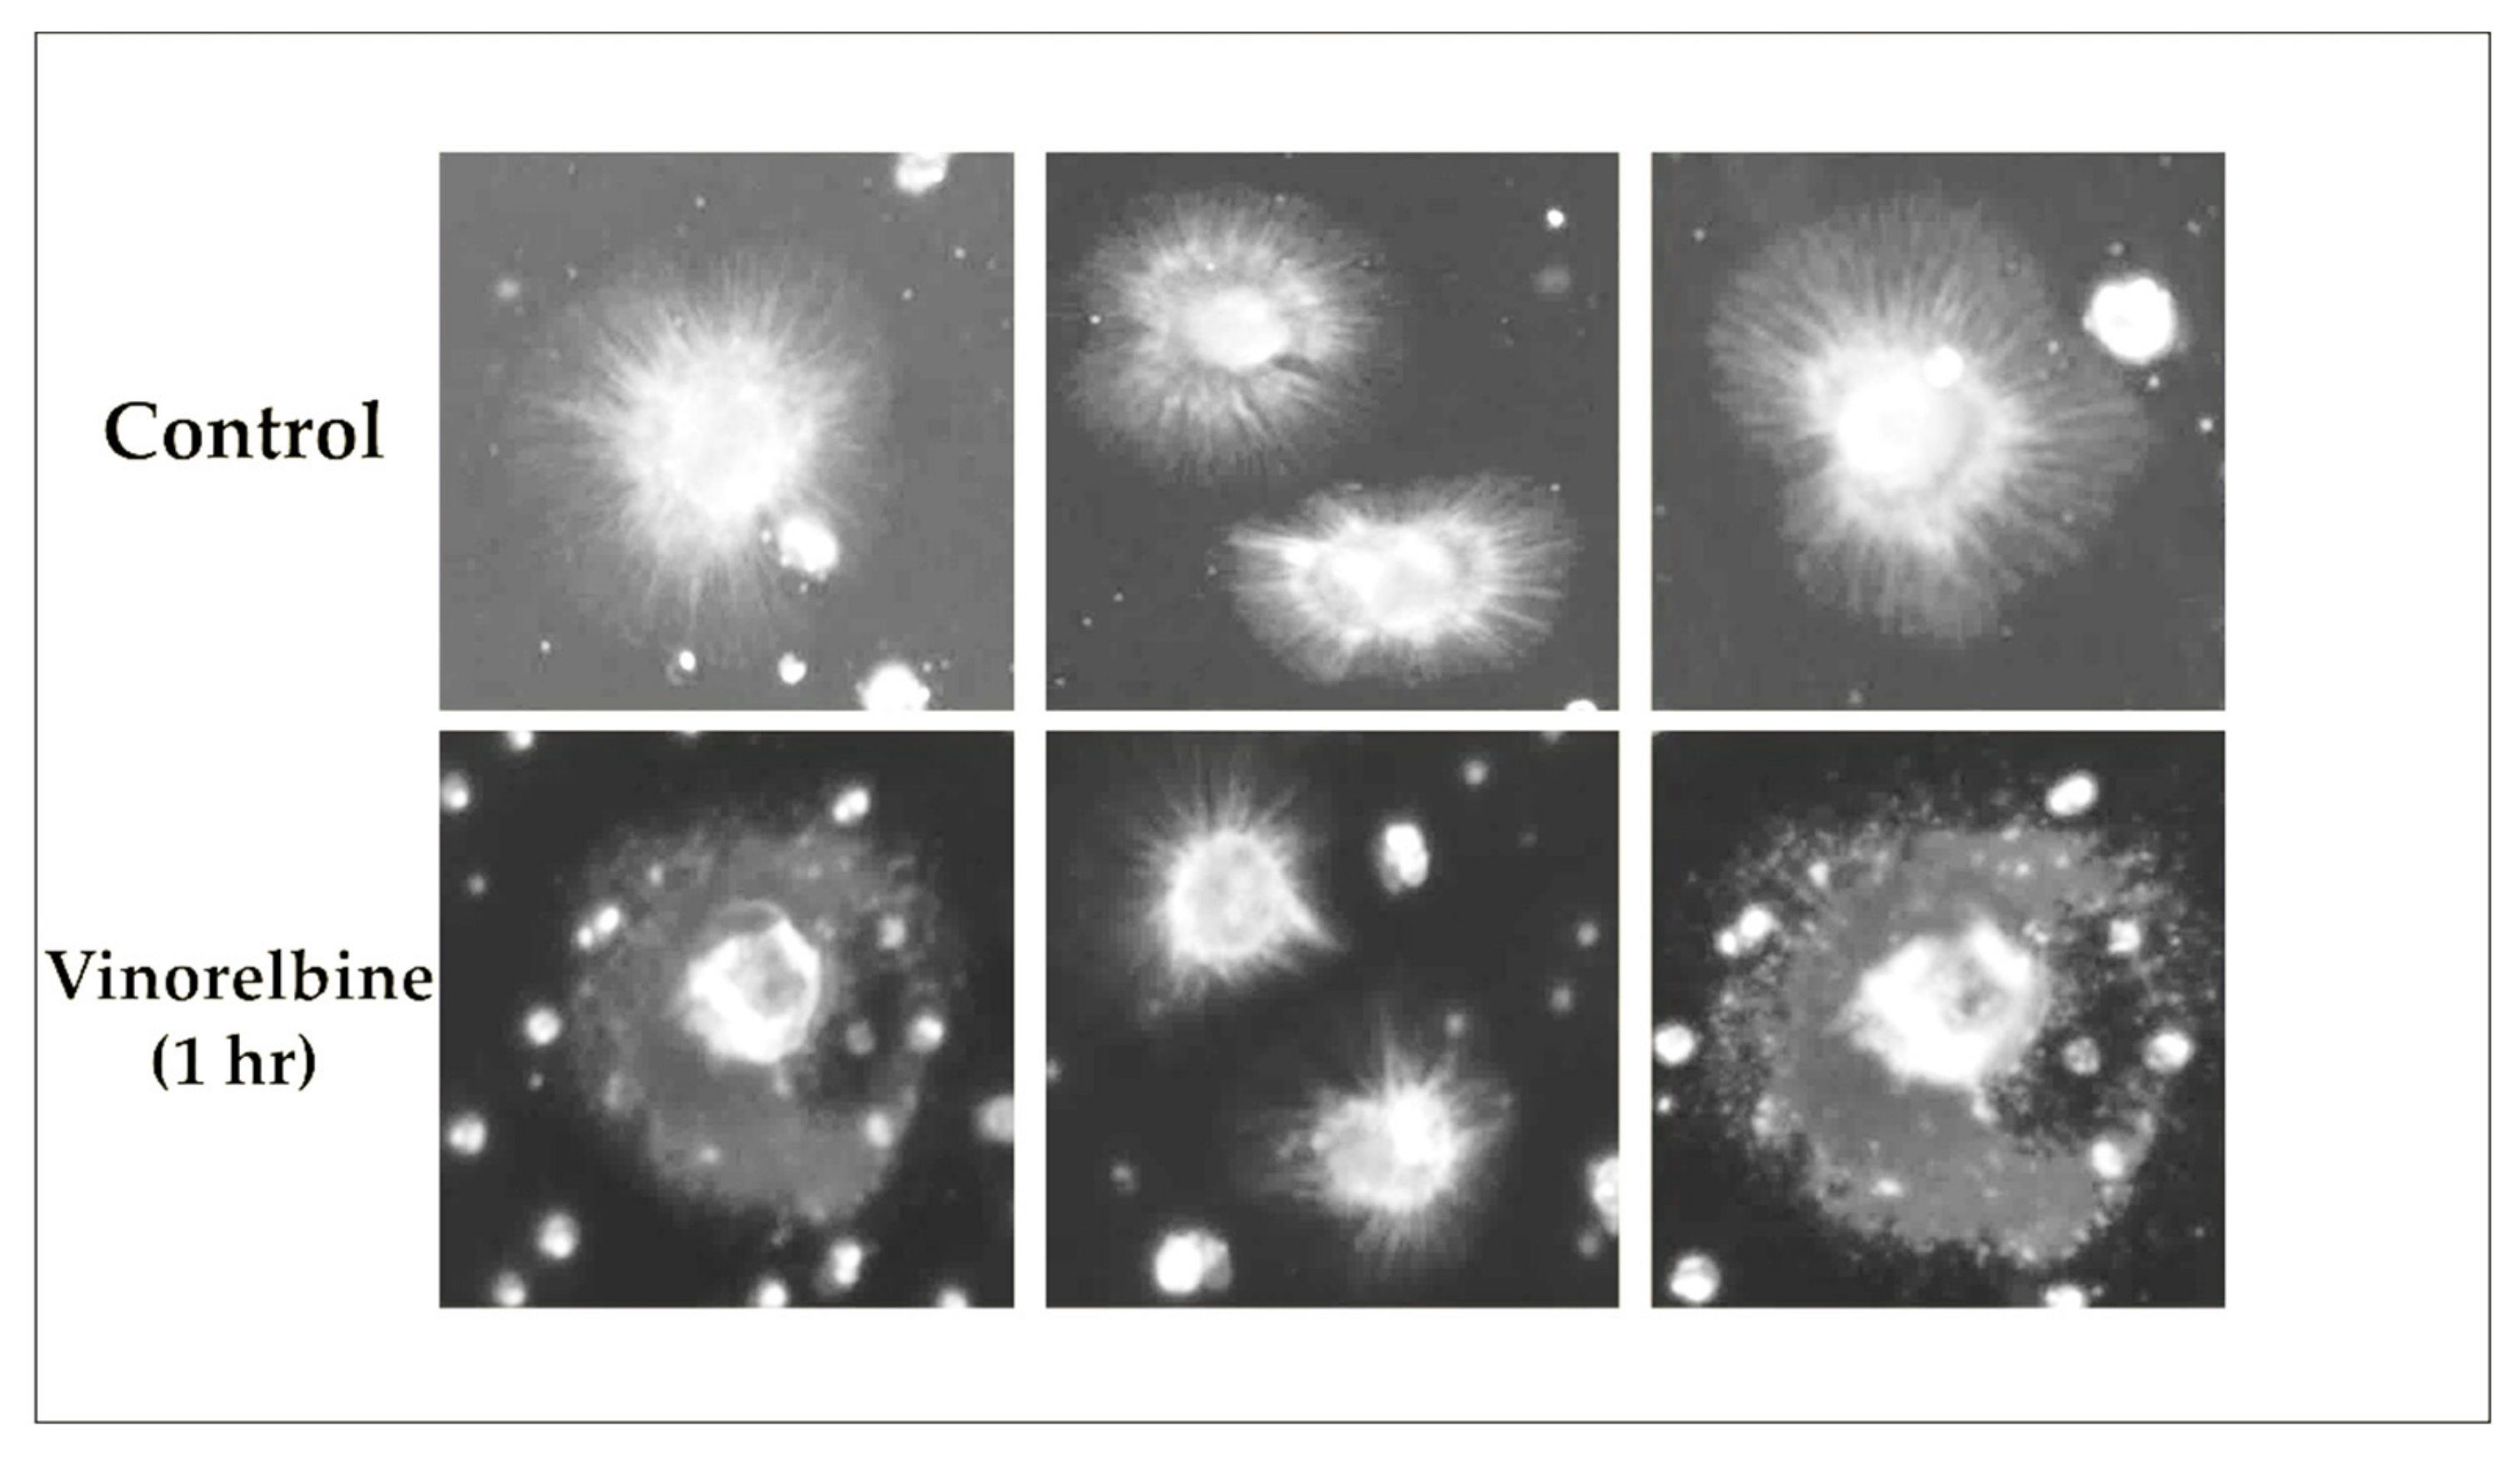

3.7. Vinorelbine Effects on McTNs